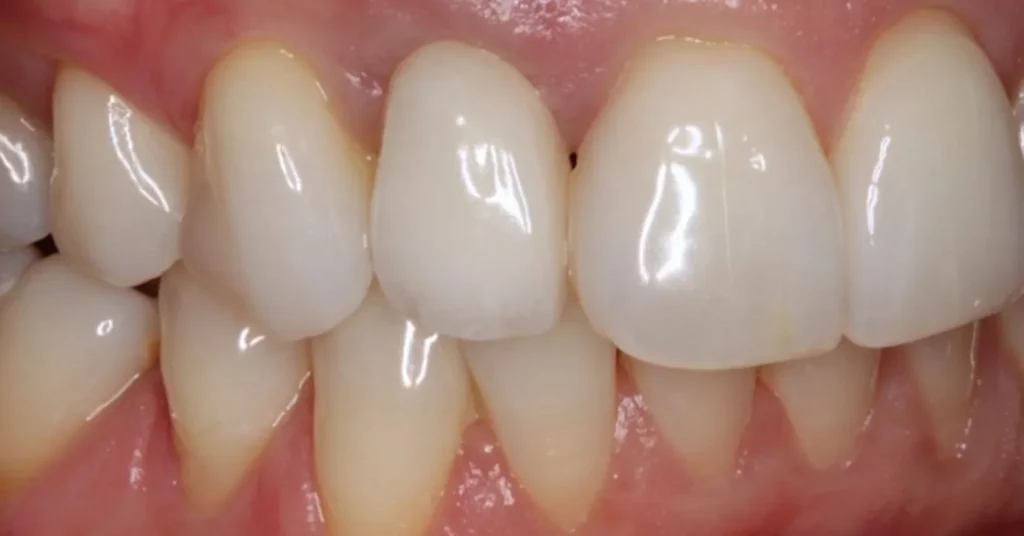

This lady attended Gentle after a previous implant had not worked. In the left photo below is a temporary bridge that kept falling out, which was frustrating for the patient, so she wanted to try again with implant treatment. Moreover, when she smiled, the adjacent eye tooth had an exposed root, so it looked too long. At the same time as placing gum around the implant, a gum graft was placed to cover the exposed eye tooth root. This improves the overall aesthetic outcome for the patient. Below on the right you can see how we took time to rebuild the bone and gum in the first phase of treatment, which gave the implant a solid foundation to sit in.

The implant was placed into the bone, under the gum, and a white post was chosen to fit into the implant to maximise the final crown’s appearance. The after photo was taken 5 years after the implant was placed and shows how nicely the work is performing.